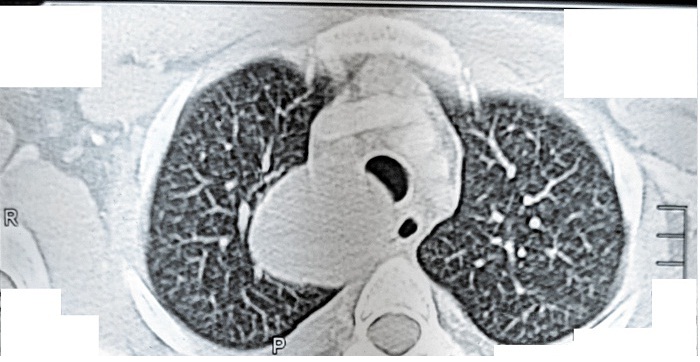

A 16-year-old boy presented with chest pain for the previous seven days that was more on the right side, gradual in onset, dull in character, intermittent, and radiating to the back. It was aggravated on exertion and was relieved with rest. The pain was associated with shortness of breath. The patient also complained of dysphagia, which was occasional and progressive. There was no history of cough or recent chest infection. General physical and systemic examinations were unremarkable. He had a low-grade fever with a hemoglobin of 13.5 g/dl, white cell count of 12.4/dL, and ESR of 52. Other routine lab investigations were within normal limits. His chest x-ray showed a right mediastinal round opacity on the right side of the carina. On his CECT scan Chest, the authors found a well-marginated nonenhancing thick fluid-attenuating lesion centered at the right paratracheal location in the middle and posterior mediastinum on the right side that was pressing on the esophagus and trachea.

Figure 2. CECT of the chest showing a round homogenous cystic lesion in the right paratracheal region pressing on the esophagus and trachea.